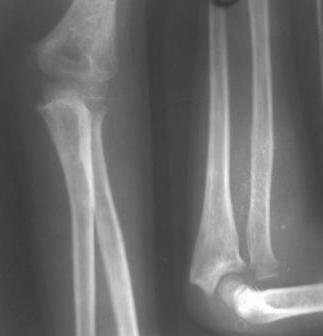

Иллюстрация к лечению застарелого повреждения Монтеджиа

Пациентка клиники детской травматологии ЦИТО

На рентненграмме видна деформация локтевой кости на границе верхней и средней трети. Ведь там был перелом.

Уважаемые коллеги, кто-нибудь еще видит здесь застарелое повреждение Монтеджи? Может мне показалось?